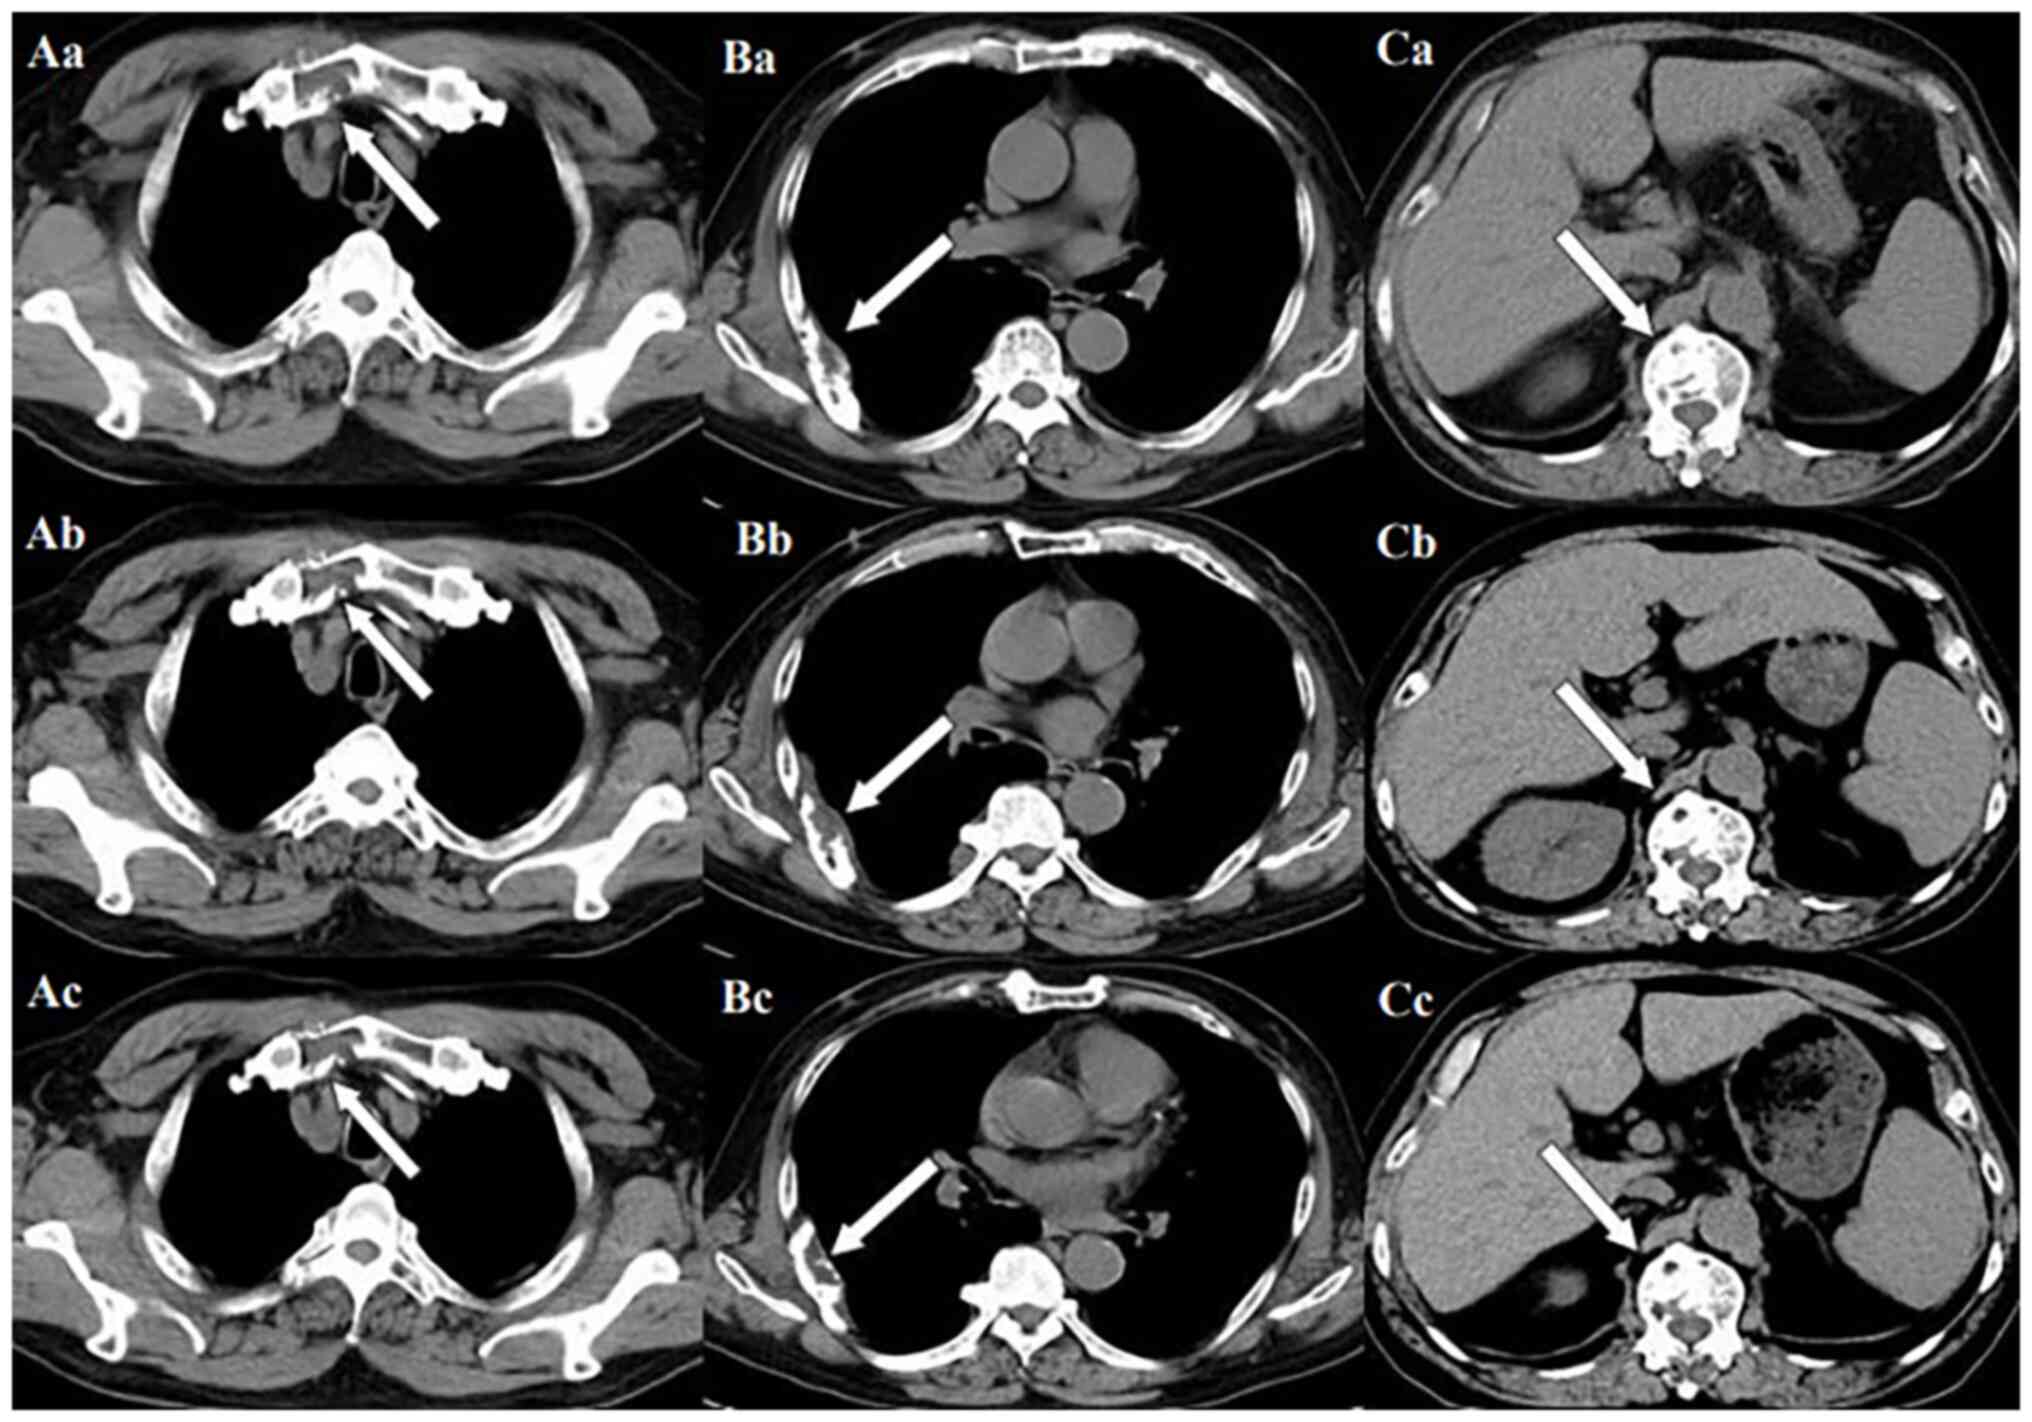

Subsequently, the patient presented with a lump around the colostomy stoma site and intermittent abdominal pain in November 2020. Physical examination revealed a lump measuring ~10×10 cm around the stoma, which did not reduce in size when the patient was lying flat. Abdominal CT (Fig. 4) revealed that the intestinal tube had protruded into the subcutaneous fat layer of the abdomen. Based on the patient's medical history, physical examination (a lump around the colostomy stoma site) and the result of abdominal CT (Fig. 4), a parastomal hernia was suspected. Surgery was the recommended treatment. Routine preoperative blood tests, coagulation function, and liver and kidney functions showed no abnormalities. Parastomal hernia repair surgery was performed using the keyhole technique in November 2020. A relatively soft drainage tube was placed subcutaneously in the surgical area. The patient recovered well after the surgery and was discharged on the third postoperative day without removing the drainage tube. During discharge, the surgical area was not compressed. However, five days after discharge, the patient experienced swelling, pain and bleeding at the surgical site. Abdominal CT showed a hematoma in the surgical area (Fig. 5). After taking hemostatic treatment measures (hemostatic drugs, compression hemostasis), fresh blood still slowly flowed out from the drainage tube. Dynamic reexamination of coagulation function showed that it gradually deteriorated, and the activated partial thromboplastin time was gradually delayed to 60 sec, which was 20 sec longer than normal (reference range, 20–40 sec). The patient had stubborn anemia, and after multiple blood transfusions, no significant increase was identified in hemoglobin, which remained between 45–68 g/l (normal range, 130–175 g/l). A bone marrow biopsy was also performed to investigate the cause of persistent bleeding (Fig. 6). The bone marrow smear was stained using the Wright staining method and 200 cells were counted under a microscope. The results showed abnormal proliferation of plasma cell lines in bone marrow smears, accounting for 35% of total cells, with an immature plasma cell composition accounting for 21.0% of total cells (normal range, 0–0.8%). This result is consistent with the diagnosis of multiple myeloma (10,11). Fig. 6 shows the characteristics of abnormal plasma cells: This type of cell was significantly different in size, with the cell body and nucleus appearing circular, elliptical, ovoid or irregular in shape. The nucleus was misaligned, the chromatin of the nucleus appeared as a granular or loose network and certain cells showed obvious nucleoli. The cytoplasm was rich, stained opaque dark blue and flame-like, with obvious light staining bands around the nucleus. Nodular protrusions and vacuoles were easily observed, while no particles were seen. The morphological features were consistent with those of MM (10). Further testing revealed elevated serum immunoglobulin A (IgA) levels of 76.7 g/l (normal range, 0.82–4.53 g/l) and significantly increased serum β2 microglobulin (β2-microglobulin) levels of 16,205 ng/ml (normal range, 604–2,286 ng/ml). Based on the results of the bone marrow puncture, the bone destruction, anemia and bleeding were attributed to MM. After consultation with a hematologist, the patient was diagnosed with MM (IgA-λ type, Durie-Salmon Stage III). The Durie-Salmon staging system is a classic staging system for MM. The staging criteria for Stage III are as follows: One or more of the following abnormalities must be present: Hemoglobin <8.5 g/dl; serum calcium >12 mg/dl; very high myeloma protein production; IgG peak >7 g/dl; IgA peak >5 g/dl; Bence Jones protein >12 g/24 h; and >3 lytic lesions on bone survey (11). The patient was transferred to the hematology department and was treated with the PCD regimen (bortezomib, cyclophosphamide, dexamethasone), chemotherapy and blood transfusion. The specific dosage of medication is calculated based on the patient's body surface area. One chemotherapy cycle is 4 weeks and this patient received 6 cycles of chemotherapy. Afterwards, the patient received maintenance treatment with bortezomib monotherapy. The seventh rib lesion invaded the surrounding soft tissue, and the interventional department performed an empty needle puncture biopsy on it. The pathological and immunohistochemical results of the puncture tissue are consistent with multiple myeloma (10). The lesion was determined to be plasmacytoma, suggesting involvement of MM (Fig. 7), and the immunohistochemical results were as follows: CD138 (+), CD38 (+), cytokeratin (CK) (−), Ki67 (15%, +), Lambda (+) and MM oncogene 1 (+) (Fig. 8). CK negativity indicated the absence of malignant cells of epithelial origin. The patient's condition gradually improved, with increasing hemoglobin levels, recovering coagulation function, absorption of the hematoma around the stoma (Fig. 9) and alleviation of bone pain. For the past 2 years, the patient has been regularly treated in the hematology department and the progression of the MM has been slow (Figs. 10 and 11). Fig. 10 is a PET/CT image of the patient diagnosed with MM one year later. The arrows in Fig. 10 indicate the metabolic status of the lesionsin the right seventh posterior rib, upper sternum, and first lumbar spine. The increased metabolism of these three main lesions is consistent with the manifestation of MM. In Fig. 11, row A represents the situation of lesion in the upper sternum at different time-points; row B shows the situation of lesion in the upper sternum at different time-points; and row C shows the situation of lesion in the upper sternum at different time-points. The arrows in Fig. 11Aa, Ba and Ca refer to the lesions of the upper sternum, the seventh rib on the right side and the first lumbar vertebra when MM was diagnosed. Fig. 11Ab-Cb shows the respective lesions 1 year after the diagnosis of MM and Fig. 11Ac-Cc shows them at 2 years after the diagnosis of MM. After comparison, the progression of these three lesions was not obvious. After treatment, the soft tissue mass around the lesion of the right seventh rib gradually became smaller. The patient has not experienced any worsening bone pain symptoms since being diagnosed with MM. The patient has been regularly visiting the hematology outpatient department. During the follow-up period, the patient's blood routine, coagulation function and serum immunoglobulin are being tested every two months, and chest CT and spinal CT examinations conducted every 6 months. During follow-up, there has been occasional mild anemia but no coagulation abnormalities.

Figure 10.

Positron emission tomography/computed tomography examination after 1 year of diagnosis of multiple myeloma. The upper sternum, right seventh rib and first lumbar spine still have obvious lesions (arrows).

Figure 11.

Images of lesions at different stages after diagnosis of MM. (Aa-Ca) Lesion images at the time of diagnosis of MM. The arrows refer to the lesions of (Aa) the upper sternum, (Ba) the seventh rib on the right side and (Ca) the first lumbar vertebra when MM was diagnosed. (Ab-Cb) Local lesions diagnosed as MM after 1 year of treatment. (Ac-Cc) Local lesions diagnosed as MM after 2 years of treatment. MM, multiple myeloma.